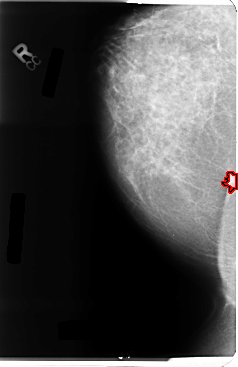

B_3054_1.RIGHT_CC

RIGHT_CC LINES 4760 PIXELS_PER_LINE 3088 BITS_PER_PIXEL 12 RESOLUTION 50 OVERLAY

FILE: B_3054_1.RIGHT_CC.OVERLAY

TOTAL_ABNORMALITIES 1

ABNORMALITY 1

LESION_TYPE MASS SHAPE IRREGULAR MARGINS SPICULATED

ASSESSMENT 4

SUBTLETY 4

PATHOLOGY MALIGNANT

TOTAL_OUTLINES 1

BOUNDARY